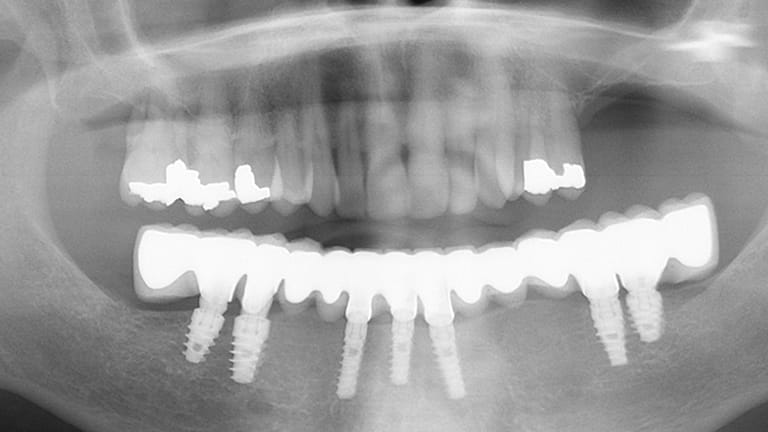

Implant Full Arch

Below is a few examples of what DENTAL IMPLANTS can do for you and your smile!